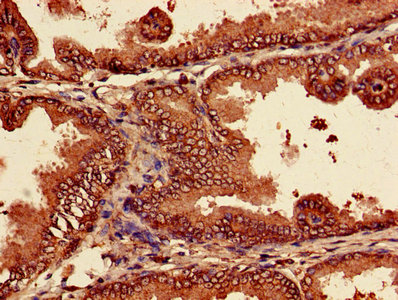

Immunohistochemistry of paraffin-embedded human prostate tissue using CSB-PA01335A0Rb at dilution of 1:100